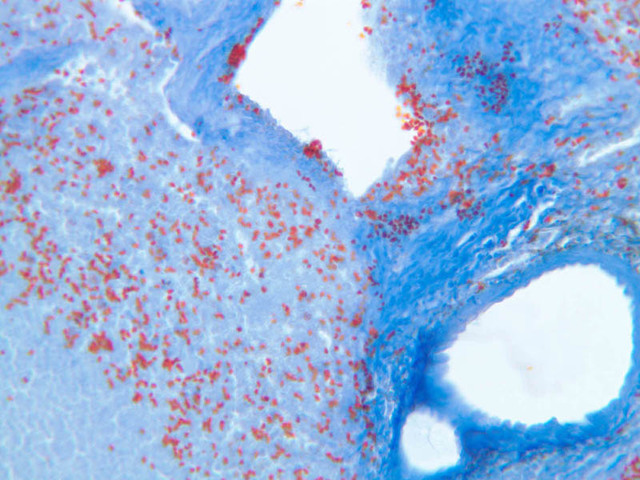

Sections through the spleen (slides A-36, aniline blue [2.5x, 10x, 20x-labeled, 40x] [2.5x, 10x-labeled, 20x-labeled, 40x]; A-37, retic [2.5x, 10x, 20x-labeled, 40x]; A- 37, H&E [2.5x-labeled, 10x, 20x, 40x]; A-38, H&E [10x, 20x, 40x]; A-39, H&E [2.5x, 10x, 20x, 40x]) show a thick investing capsule composed of collagenous tissue and smooth muscle, typically covered with mesothelium. In slide A-36 muscle and collagen are brightly stained. The capsule and mesothelium completely surround the organ and the fibrous portion enters the splenic substance at the hilus around the splenic arteries and veins forming trabeculae of fibromuscular tissue within the splenic substance. This fibromuscular tissue enables the spleen to expel blood by contracting. Identify trabeculae as fibrous partitions in the section and look for blood vessels within them.

Where the trabecular arteries pass into the splenic pulp, they become invested by a sleeve of lymphoid tissue. This lymphatic tissue collectively forms the white pulp of the spleen (A-36 [2.5x, 10x, 20x, 40x]). It also is referred to as the periarterial lymphatic sheath or PALS. On an H&E stained section (A-38 [2.5x, 10x, 20x, 40x] [2.5x, 10x, 20x, 40x]) the white pulp will appear as basophilic clumps of lymphoid cells. The arteries of the white pulp are called central arteries, although they may be displaced to one side of the lymphoid sleeve by the presence of a nodule. The majority of cells forming the PALS are T lymphocytes. In places the covering of lymphatic tissue is enlarged due to the presence of lymphoid nodules (splenic or Malphighian corpuscles) which are comprised predominantly of B lymphocytes.

The remainder of the cellular mass in the spleen is red pulp (A-38 [10x, 20x, 40x]), made up of red and white cells of the blood enmeshed in the reticular tissue of splenic cords and present in the splenic sinuses. After passing through the PALS, the trabecular arteries branch to form smaller arterial vessels known as penicillar arterioles which narrow, forming arterial capillaries that empty into the cords of the red pulp (open circulation) or into the venous sinuses (closed circulation). In the splenic sinuses the cells of the blood are exposed to red pulp macrophages. The splenic sinuses eventually become confluent to form veins that enter the trabeculae and gradually merge meeting in the hilus to form splenic veins.

Examine the composition of the red pulp tissue. The three dimensional structure of the red pulp is analogous to Swiss cheese with the holes being the venous sinuses and the cheese being the parenchyma (i.e. splenic cords). On slide A-36 which is stained with Mallory's aniline blue locate examples of the splenic sinuses ([2.5x, 10x, 20x, 40x-labeled] [10x, 20x, 40x]). The walls of the splenic sinuses consist of adjoining specialized endothelial cells whose nuclei in many cases stand out from the wall in a bead-like fashion. The basement membrane of the epithelial cells stains blue revealing the sinuses quite nicely. Usually the sinus lumen is filled with red cells and leukocytes. The skeletal framework of the cords is provided by a network of reticular fibers. As above, the reticular cells are best seen using a reticular fiber stain (slide A-37 [2.5x, 10x, 20x, 40x-labeled]). Look for the large pale nuclei of reticular cells that have darkly stained reticular fibers. Fibers run irregularly in the cords, but clearly outline the sinuses around which they are wrapped. Notice on this same slide that there is much less reticular tissue in the white pulp than the red. The splenic cords occur around the sinuses and are distinguished by the presence of disintegrating red blood cells undergoing phagocytosis.